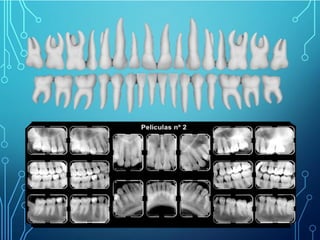

En la técnica de paralelismos utilizamos como receptor las películas

radiográficas o sensores digitales. En un estudio completo en un adulto

utilizamos 16 películas radiográficas; 8 superiores y 8 inferiores y además 4

interproximales.

Las películas radiográficas que utilizamos en la técnica de paralelismo

tienen diferentes tamaños. En niños utilizamos la número 0. En adultos, en

el sector anterior se usa la numero 1 de manera vertical y en posterior la

numero 2 de forma horizontal.